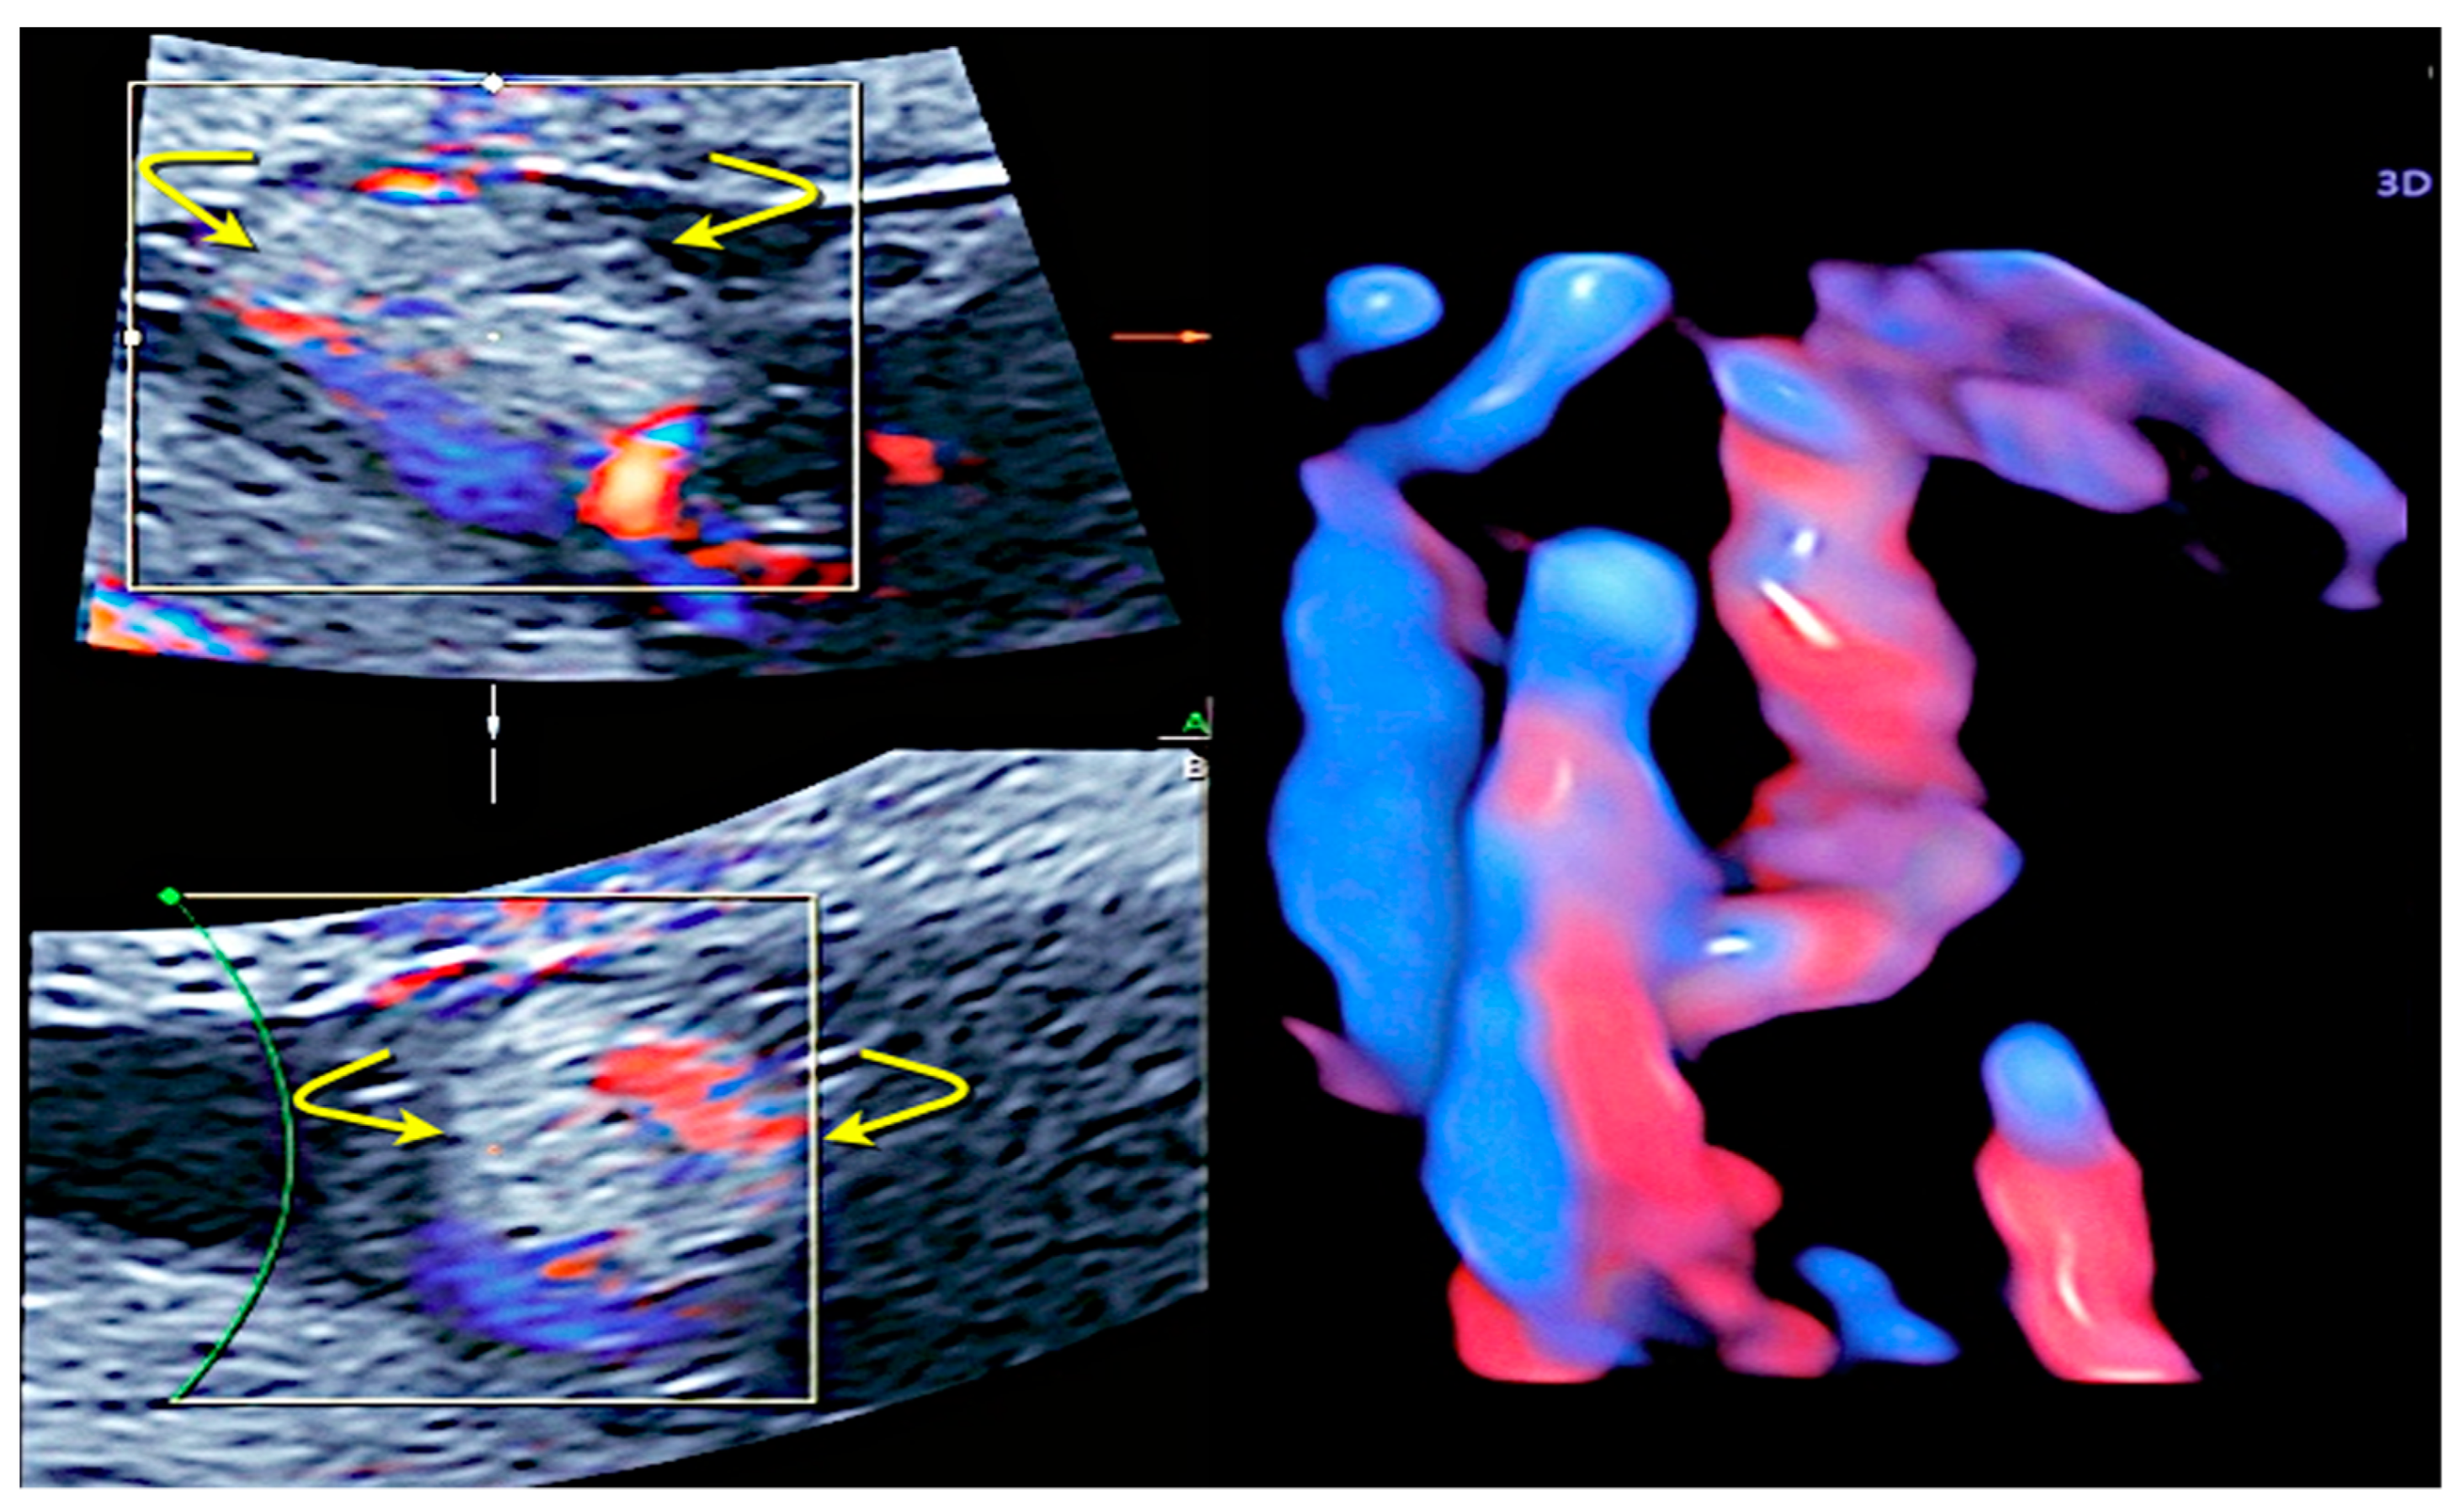

3.1. Cord Coiling